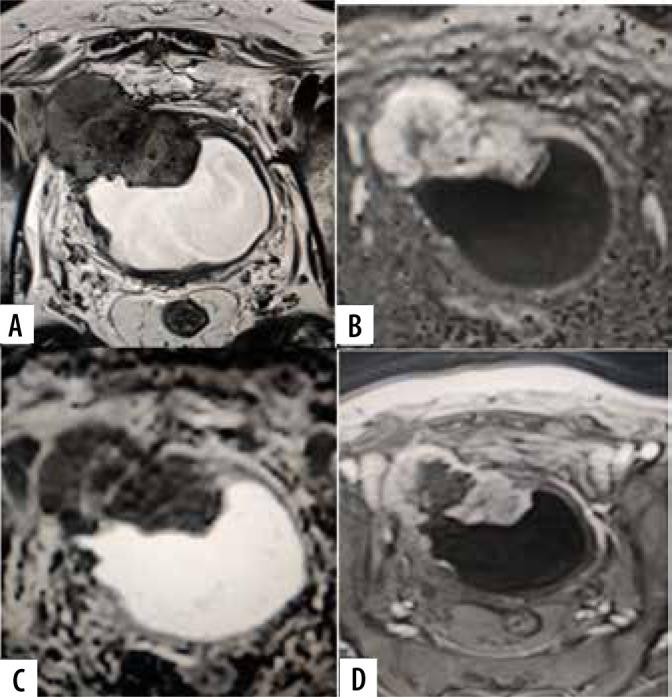

The purpose of the present study was to assess the diagnostic accuracy of the Vesical Imaging-Reporting and Data System (VI-RADS) scoring system in predicting muscle infiltration of bladder cancer (BC) on a pre-operative multiparametric magnetic resonance imaging (mpMRI).

The prospective study enrolled patients with bladder lesions detected on a preliminary ultrasonography or cystoscopy. The patients underwent mpMRI on a 3T MRI scanner followed by surgery within 2 weeks. The tumours were assigned a VI-RADS score by 2 experienced abdominal radiologists. The VI-RADS score was compared with postoperative histopathological findings to confirm detrusor muscle infiltration. The diagnostic performance of VI-RADS for predicting muscle invasion was assessed by calculating sensitivity, specificity, positive predictive value (PPV), negative predictive value (NPV) and accuracy.

A total of 60 patients were included in the study with a male: female ratio of 4.4 : 1. Transurethral resection of bladder tumour (TURBT) was performed in 47 (78.4%) and radical cystectomy in 13 (21.6%) patients. 19 (31.7%) had non-muscle invasive invasive BC (NMIBCa) and 41 (68.3%) had muscle invasive BC (MIBCa) on histopathology. There was a significant association between VI-RADS score and its components with muscle invasion ( < 0.05). A VI-RADS score of ≥ 3 had a sensitivity of 97.56% (95% CI: 0.87-0.99%), specificity of 73.68% (95% CI: 0.49-0.91), positive predictive value of 88.9% (95% CI: 0.79-0.94), negative predictive value of 93.33% (95% CI: 0.66-0.99), and diagnostic accuracy of 90% (95% CI: 0.80-0.96) for prediction of muscle invasion.

VI-RADS scoring system pre-operatively predicts the likelihood of muscle invasion in BC with a satisfactory diagnostic performance, and it should be incorporated in the diagnostic work-up of BC patients.